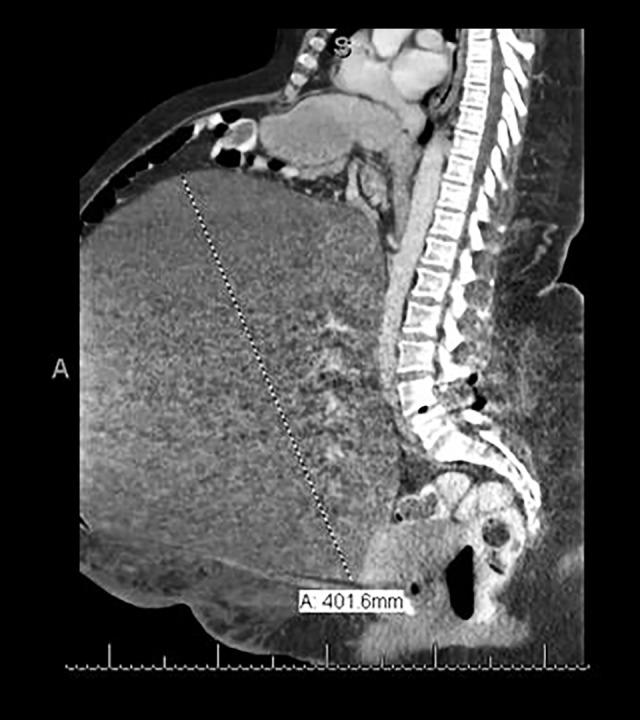

BACKGROUND Mucinous cystadenoma is a benign cystic ovarian tumor arising from the surface epithelium of the ovary; it usually presents with vague, unspecific abdominal symptoms. If not detected early, they have the potential to grow to a substantial size and can present with huge abdominal distention leading to various compression symptoms. Mucinous cystadenomas most commonly occur in the third to sixth decades of life, and rarely occur in extremes of age. The reported incidence of giant ovarian cystadenoma in postmenopausal women is low or relatively unknown due to widespread use of ultrasound and other radiological imaging modalities these days. Here, we report a case of giant mucinous cystadenoma in a 72-year-old postmenopausal woman with multiple comorbidities. CASE REPORT We present the case of a 72-year-old postmenopausal high-risk patient who presented with a huge abdominal distention which started gradually 1 year before. Abdominopelvic ultrasound showed a left giant multiloculated abdominal cyst. An intact 27-kg ovarian cyst was removed, and a total abdominal hysterectomy (TAH) along with bilateral salpingo-oophorectomy (BSO) was performed. The final histopathological report showed a benign ovarian mucinous cystadenoma. CONCLUSIONS Mucinous cystadenoma is a benign neoplastic disease that can reach a massive size. They are rare in the postmenopausal age group, but when they do occur, they pose a diagnostic and therapeutic challenge. This case report highlights the importance of early detection and management of adnexal masses in postmenopausal high-risk patients to decrease preoperative and postoperative complications and improve quality of life.

黏液性囊腺瘤是一种起源于卵巢表面上皮的良性囊性卵巢肿瘤;通常表现为模糊、非特异性的腹部症状。如果未早期发现,它们有可能生长到很大的尺寸,并可出现巨大的腹部膨隆,导致各种压迫症状。黏液性囊腺瘤最常发生在30至60岁之间,在极端年龄时很少发生。由于如今超声和其他放射成像方式的广泛应用,绝经后妇女中巨大卵巢囊腺瘤的报告发病率较低或相对未知。在此,我们报告一例72岁绝经后患有多种合并症的巨大黏液性囊腺瘤病例。病例报告:我们呈现一例72岁绝经后高危患者的病例,该患者出现巨大腹部膨隆,始于1年前并逐渐加重。腹盆腔超声显示左下腹巨大多房性囊肿。切除了一个完整的27千克卵巢囊肿,并进行了全腹子宫切除术(TAH)及双侧输卵管卵巢切除术(BSO)。最终组织病理学报告显示为良性卵巢黏液性囊腺瘤。结论:黏液性囊腺瘤是一种可长得很大的良性肿瘤性疾病。它们在绝经后年龄组中罕见,但一旦发生,会带来诊断和治疗挑战。本病例报告强调了在绝经后高危患者中早期发现和处理附件肿块对于减少术前和术后并发症以及改善生活质量的重要性。